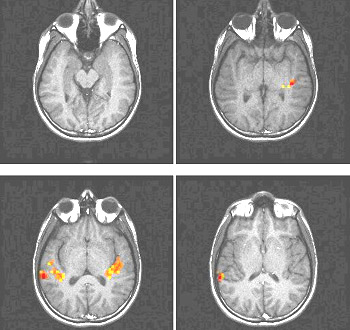

ON: Passive hearing music (single notes, unfamiliar tune), in binaural-monophonic presentation OFF: Hearing the background noise